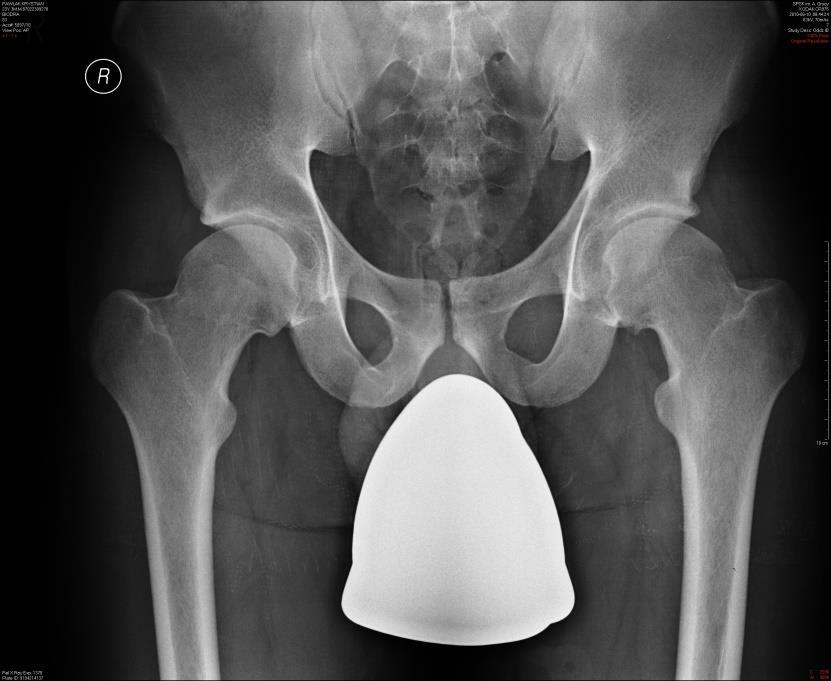

Do charakterystycznych objawów podmiotowych i przedmiotowocyh patologii widocznej na radiogramach należą: 1) ból w pachwinie promieniujący na przednią powierzchnię uda; 2) objaw Kleina-Trethowana; 3) objaw Capenera-Durbina; 4) objaw Drehmanna; 5) objaw Gage. Prawidłowa odpowiedź to:

Pytanie 73